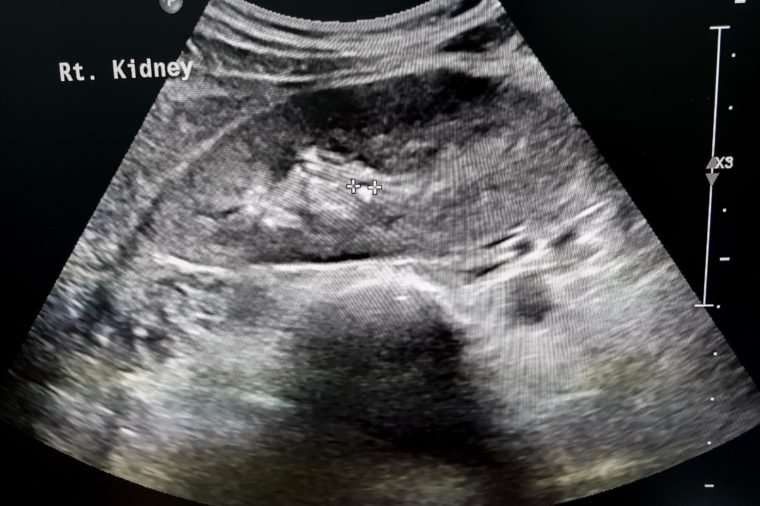

حصى الكلى

عادة ما يصف الناس هذا بأنه “أسوأ ألم في حياتي”: حصوات الكلى (وتسمى أيضًا التهاب الكلية) عبارة عن رواسب معدنية وملحية صلبة تتشكل داخل الكلى؛ الطريقة الوحيدة لإخراجها هي الانتظار حتى تمر عبر المسالك البولية.

بناءً على حجم الحجر وموقع انسداد المسالك البولية، قد يكون لدى المرضى الجانب الأيمن أو الأيسر مما يؤدي إلى الطعن وآلام أسفل البطن.

يمكن أن تكون خيارات العلاج رعاية داعمة (ترطيب، إدارة الألم) والسماح بمرور الحجر وهو أمر فعال لمعظم المرضى. يمكن للأطباء استخدام علاج موجة الصدمة أو أشعة الليزر لتشريح الحجارة وتسهيل المرور والإزالة.